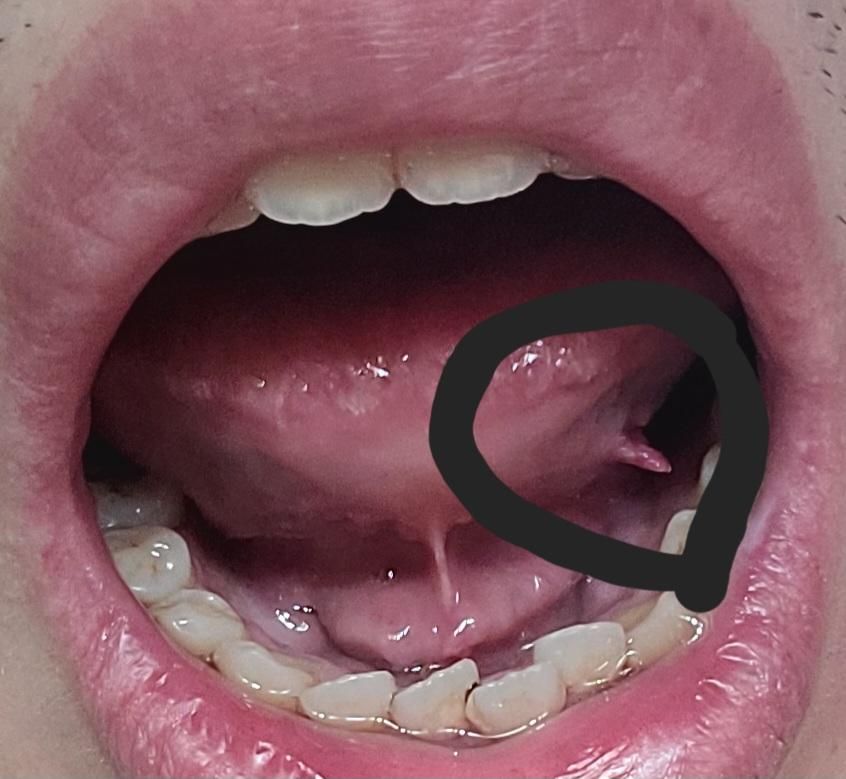

혓바늘인줄 알고 살펴봤는데 혀 돌기가 떨어지려 합니다

13일 어제부터 혀가 좀 아팠어요. 혓바늘이겠지 대수롭지 않게 생각하고 오늘 거울보며 살펴봤더니 혀 밑부분 돌기(?)라고 해야하나요? 그 부분이 사진처럼 좀 떨어져 있습니다. 이런적이 한 번도 없어서 너무 무섭네요. 통증도 있어요. 일단은 알보칠이 집에 있어서 환부에 좀 발랐는데 어떻게 해야하나요?

일시적인 손상 및 구내염일 가능성이 가장 큽니다. 해당 부분에 손상이 있었는데 자극에 의해 환부가 커졌을 가능성도 있습니다. 다만 해당 사진만으로는 정확히 알 수 없으므로 지금 상태가 2주 이상 지속된다면 가까운 치과 방문 후 검사를 해보시길 바랍니다.

혓바늘이 난곳이 계속해서자극을 받아서 그런거 같습니다. 시간이 지나면 괜찮아질테니 당분간은 자극이 가지 않도록만 해주세요.

해당부위가 어떤 원인에 의해 지속적으로 자극을 받아 생긴 상피증식이 아닐까 싶지만 자세한 건 치과에서 조직검사를 해보는 것을 추천드립니다